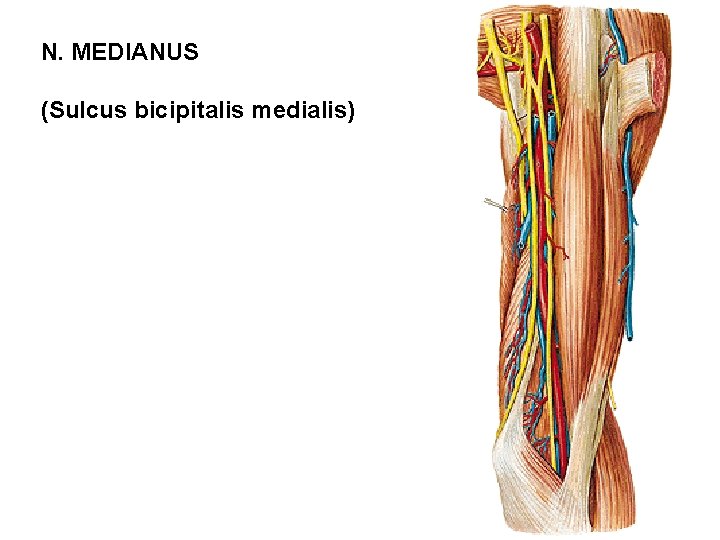

N. MEDIANUS (Sulcus bicipitalis medialis)

N. MEDIANUS - rr. articulares - rr. musculares - m. pronator teres - m. flexor carpi radialis - m. palmaris longus - m. flexor digitorum spf. - n. interosseus antebrachii ant. - m. flexor pollicis longus - radial half of m. flexor dig. prof. - m. pronator quadratus - r. palmaris